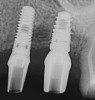

Apparently with time, stable implants placed with low initial torque develop bone characteristics around them that are similar to sites where implants were placed with a high initial torque (Figure 4 and Figure 5). Conversely, for implants placed with a high initial torque, the healing process, despite the high initial torque, provides a level of biologic stability that is not necessarily influenced by the initial insertion torque value.

Fig 5. Radiograph of the implant at site No. 28 (shown in Figure 4) with an oversized cover screw, which was used to assist in stabilizing the implant within the osteotomy.

Figure 5